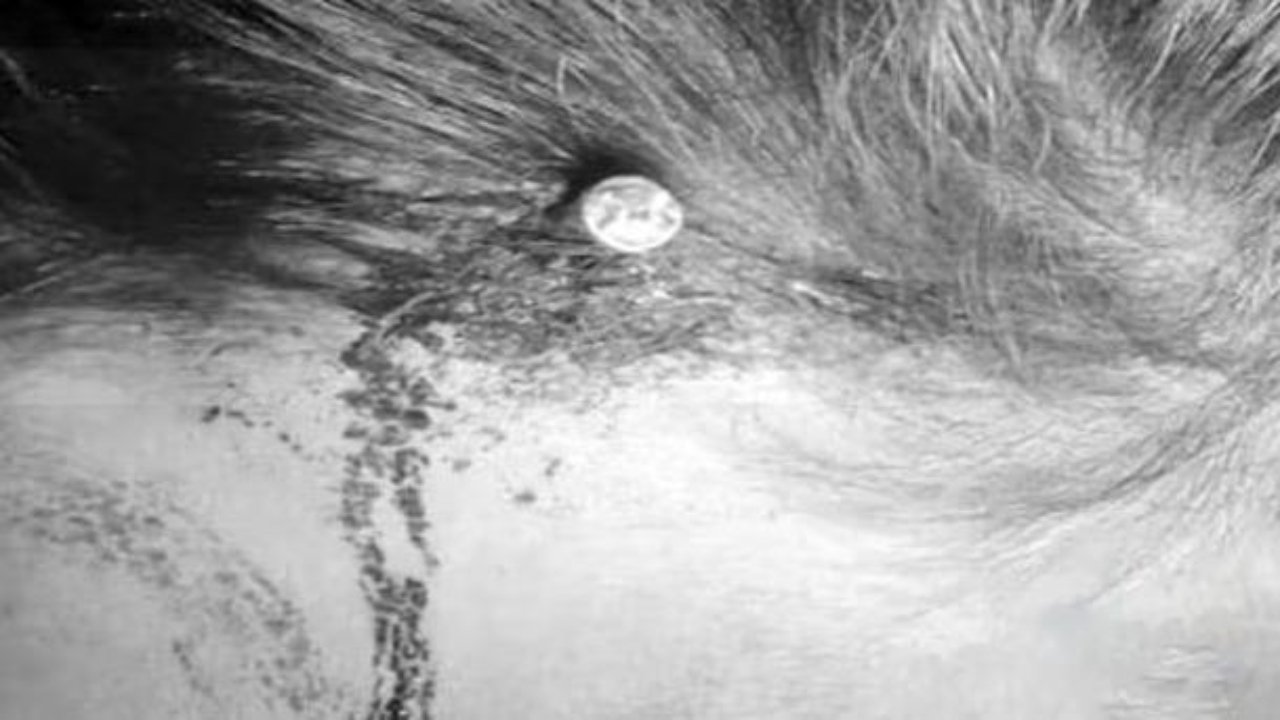

She got injured and was rushed to Lady Reading Hospital, and underwent emergency surgery to remove the nail from her skull.

The woman left the hospital with her family after the nail was removed from her head.